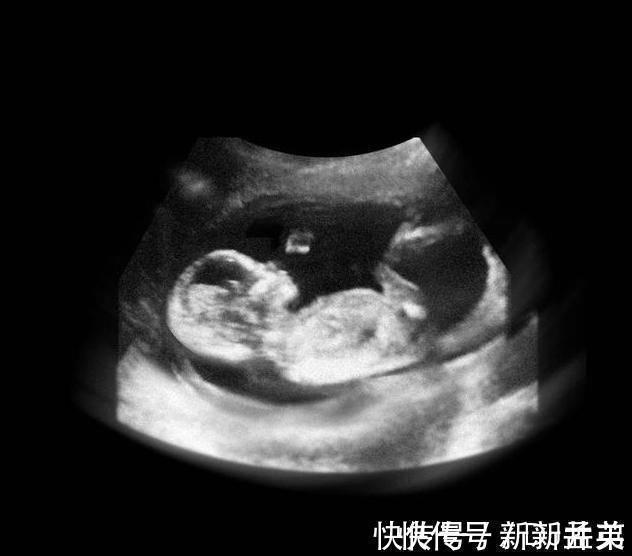

进入12周,胎儿开始在羊水中又动了,骨骼发育开始坚硬,宝宝的四肢开始做很多动作,肾脏开始分泌尿液,肝脏开始分泌胆汁,维持生命的重要器官更多地开始工作了。